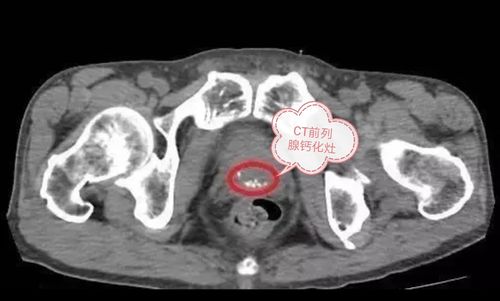

前列腺内见钙化灶什么意思

前列腺内就可以发现少量的精钙化灶,这些精钙化灶多呈串珠状,还可以出现小段结节。这些精钙化灶可以出现在尿道上、肛门周围,还可以通过颈部用手、前胸后背都可以感受到。